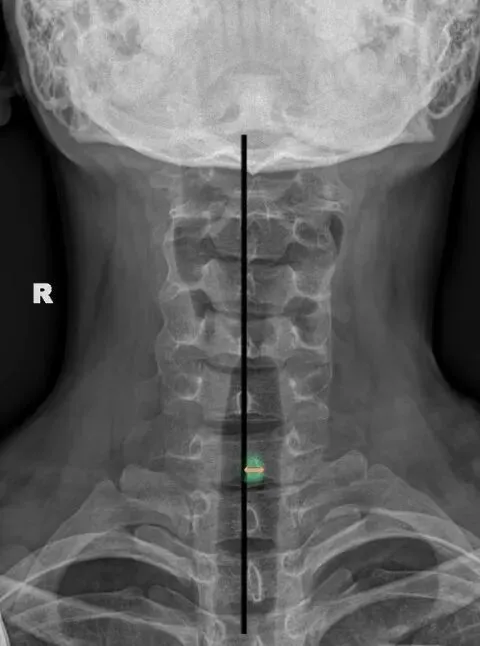

六旋指颈椎旋转,需结合颈椎正侧位观察。

颈椎正位主要观察棘突有没有偏歪,有没有在棘突中心轴线的连线上。

如果某一节椎骨的棘突中心点偏离,各棘突中心连线大于等于3毫米,则表示该节段颈椎有轴向旋转。

侧位主要观察椎体有没有双边征和关节突有没有双突征。

造成这两个征象的原因就是椎体后缘及双侧关节突没有完全重叠,摄影体位不标准时也会出现这种现象。所以我们要结合正侧位观察,如果正位没有出现某节段颈椎棘突偏移,但是侧位出现颈椎双凸或双边征时,大概率就是摄影体位不标准。反之正位能看到某节段颈椎棘突偏移,同时侧位能看到对应节段颈椎的双边或者双凸征时,基本可以确定椎体存在旋转。